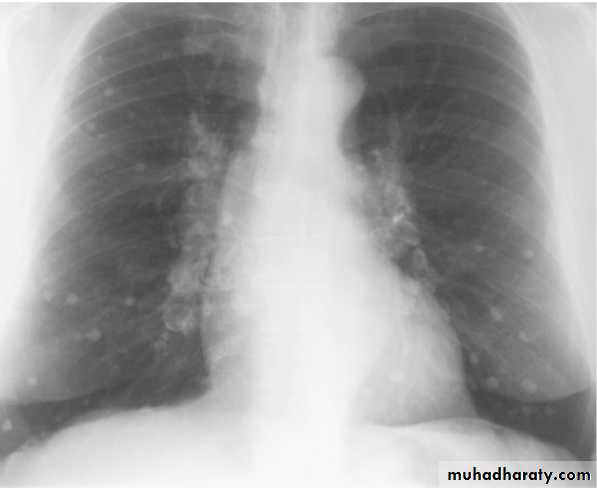

•Differential diagnosis of multiple spherical lesions:

1 - Metastasis.2-Hydatid cyst.

3- Sarcoidosis.

4- Rheumatoid nodules.

5 – pneumoconiosis

6- Histoplasmosis

Chest X-ray shows radio-opaque (white) nodular lesion in the right mid-lung field.

Dx:x chicken pox , Histoplasmosis (calcified granuloma).CAVITARY LESIONS